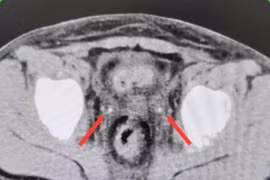

Kẹt sỏi niệu quản ở trẻ sau mổ viêm ruột thừa gây suy thận

Đây là một tình huống cấp cứu nguy hiểm nhưng nếu được chẩn đoán và điều trị kịp thời, chức năng thận có thể hồi phục hoàn toàn hoặc gần hoàn toàn.